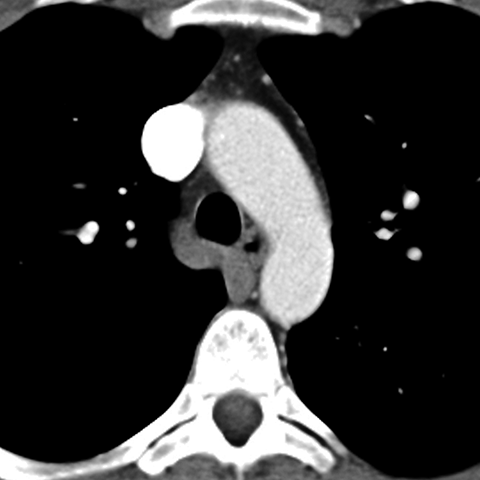

Normal antomy of the aorta (Axial CT) [3 of 5]